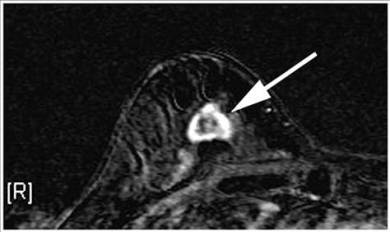

Doctors have successfully dropped the first “smart bomb” on breast cancer, using a drug to deliver a toxic payload to tumor cells while leaving healthy ones alone. In a key test involving nearly 1,000 women with very advanced disease, the experimental treatment extended by several months the time women lived without their cancer getting worse.

A warning to hopeful patients: the drug is still experimental, so not available yet. Its backers hope it can reach the market within a year. The treatment builds on Herceptin, the first gene-targeted therapy for breast cancer. It is used for about 20 percent of patients whose tumors overproduce a certain protein. Researchers combined Herceptin with a chemotherapy so toxic that it can’t be given by itself, plus a chemical to keep the two linked until they reach a cancer cell where the poison can be released to kill it.

This double weapon, called T-DM1, is called the “smart bomb.” Doctors tested T-DM1 in 991 women with widely spread breast cancer that was getting worse despite treatment with chemotherapy and ordinary Herceptin and found that T-DM1 caused fewer side effects than the other drugs did. “People don’t lose their hair, they don’t throw up. They don’t need nausea medicines, they don’t need transfusions,” said Blackwell, who has consulted in the past for Genentech, the study’s sponsor.